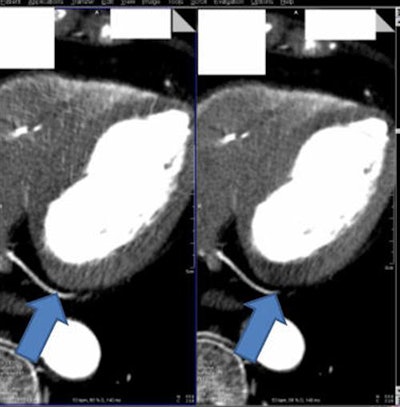

Myocardial CT image (above right) reconstructed without beam hardening correction kernel. Distinct beam-hardening artifact, mimicking hypodensity, such as found in myocardial infarct, is visible. The inhomogeneous dorsal wall of the left ventricle represents a possible myocardial infarct. The patient cannot be discharged and undergoes further (possibly) invasive examinations. Image above left shows same anatomy with beam-hardening correction algorithm applied. Homogeneous dorsal wall of the left ventricle confirms no myocardial infarct. With a high certainty in diagnosis, the patient can be discharged. Images below and bottom depict iodine maps of the same anatomy with no beam-hardening correction applied. All images courtesy of Drs. Albrecht Moritz and U. Joseph Schoepf.When the algorithm was employed, the group found significantly lower overall mean myocardial attenuation than without it. Relative differences from average myocardial attenuation were also smaller with use of the algorithm (p < 0.01) (European Radiology, September 2016, Vol. 26:9, pp. 3,215-3,222.)